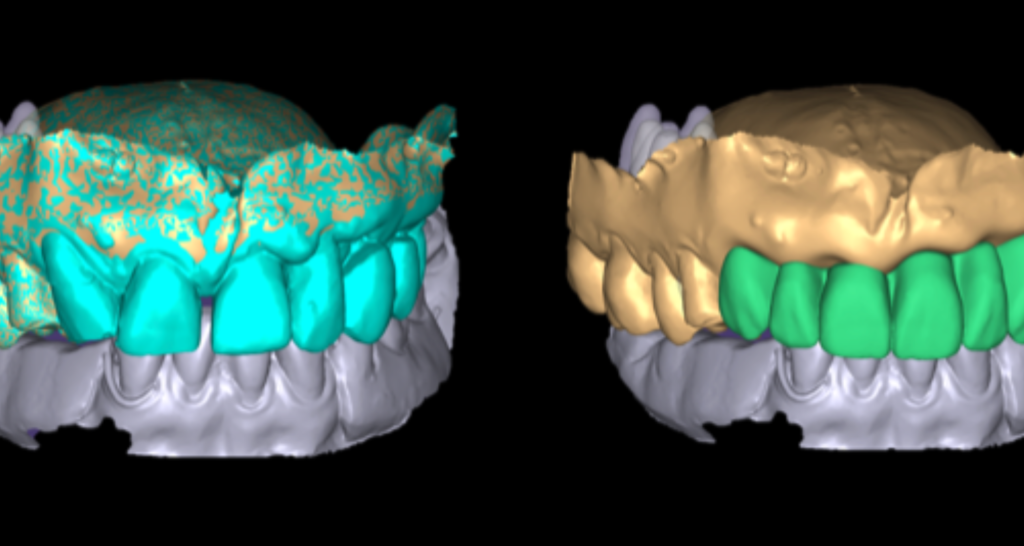

Scanner et digital work flow

la numérisation de documents physiques à l’aide d’un scanner ou d’un appareil similaire, suivi d’une gestion efficace de ces documents numérisés tout au long de leur cycle de vie. Ce concept est particulièrement important à l’ère numérique, où de nombreuses entreprises cherchent à réduire leur utilisation de documents papier et à améliorer leur efficacité opérationnelle.